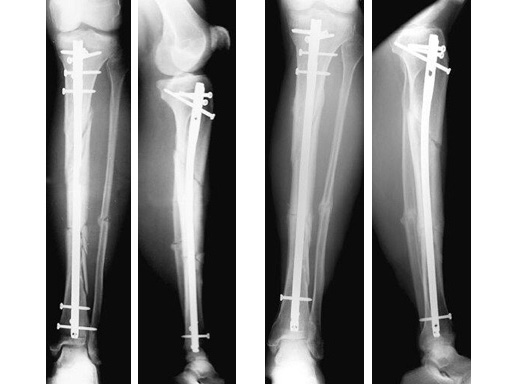

47-year-old man with closed 42-C3 fracture following a sports accident treated with ETNS.